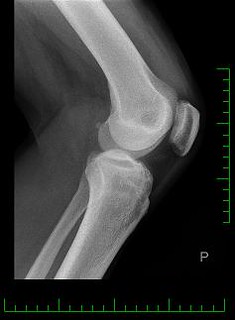

콘드로이친은 주로 관절을 둘러싼 연골을 구성하는 물질로, 젊었을때는 체내에서 잘 생성되지만 연령이 증가하면서 체내에서 합성하는 능력이 저하되어, 중년이 되면 몸에서 필요한 양의 5% 밖에 생성되지 않는다고 합니다. 콘드로이친이 결핍되면 연골의 탄력이 떨어지고 닳을 수 있기 때문에 하루 1200mg의 섭취가 권장됩니다.콘드로이친 1200mg 효능

연구에 따르면 콘드로이친은 관절 건강에 상당한 효능을 보일 수 있다고 합니다. 콘드로이친 1200mg의 효능으로는 관절 통증을 줄이고, 관절 기능을 향상시키며, 골관절염의 진행을 늦추는 데 효과가 있다고 합니다.

콘드로이친 1200mg은 연골에 물을 끌어들여 충격 흡수 능력을 높이고, 이를 통해 관절 건강을 증진시킨다고 알려져 있습니다.